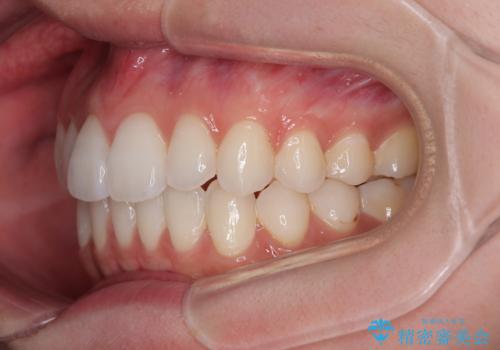

上下前歯の突出感とデコボコを気にして来院された患者様です。

インビザラインによる上下歯列の側方拡大と後方移動、必要に応じてIPR(歯と歯の間を削る)によりスペースの獲得により歯列を整えることとしました。

治療途中、出産や転居があり、2年ほど治療期間が長くなってしまいましたが、前歯の歯並びや飛び出した感覚を無事に改善させることができました。